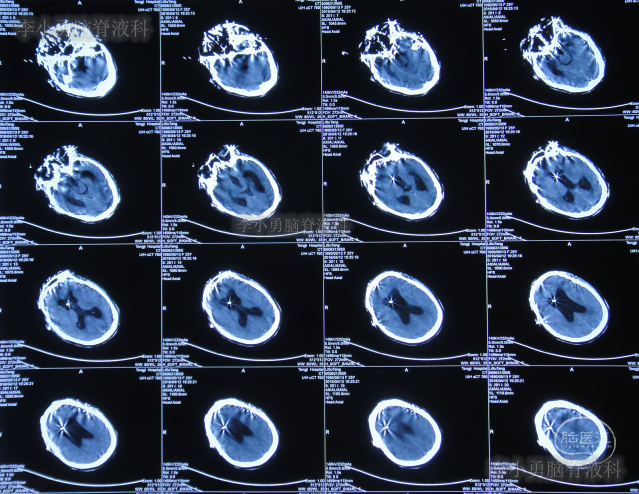

第三家医院第2次建议回家观察1周后即2016年4月3日,症状仍未缓解反而越来越重,于是,就诊于第四家位于上海市徐汇区的某三甲医院,查头颅CT后(图-2)“认为无明显异常”,怀疑癫痫。

图-2:2016年4月3日头颅CT